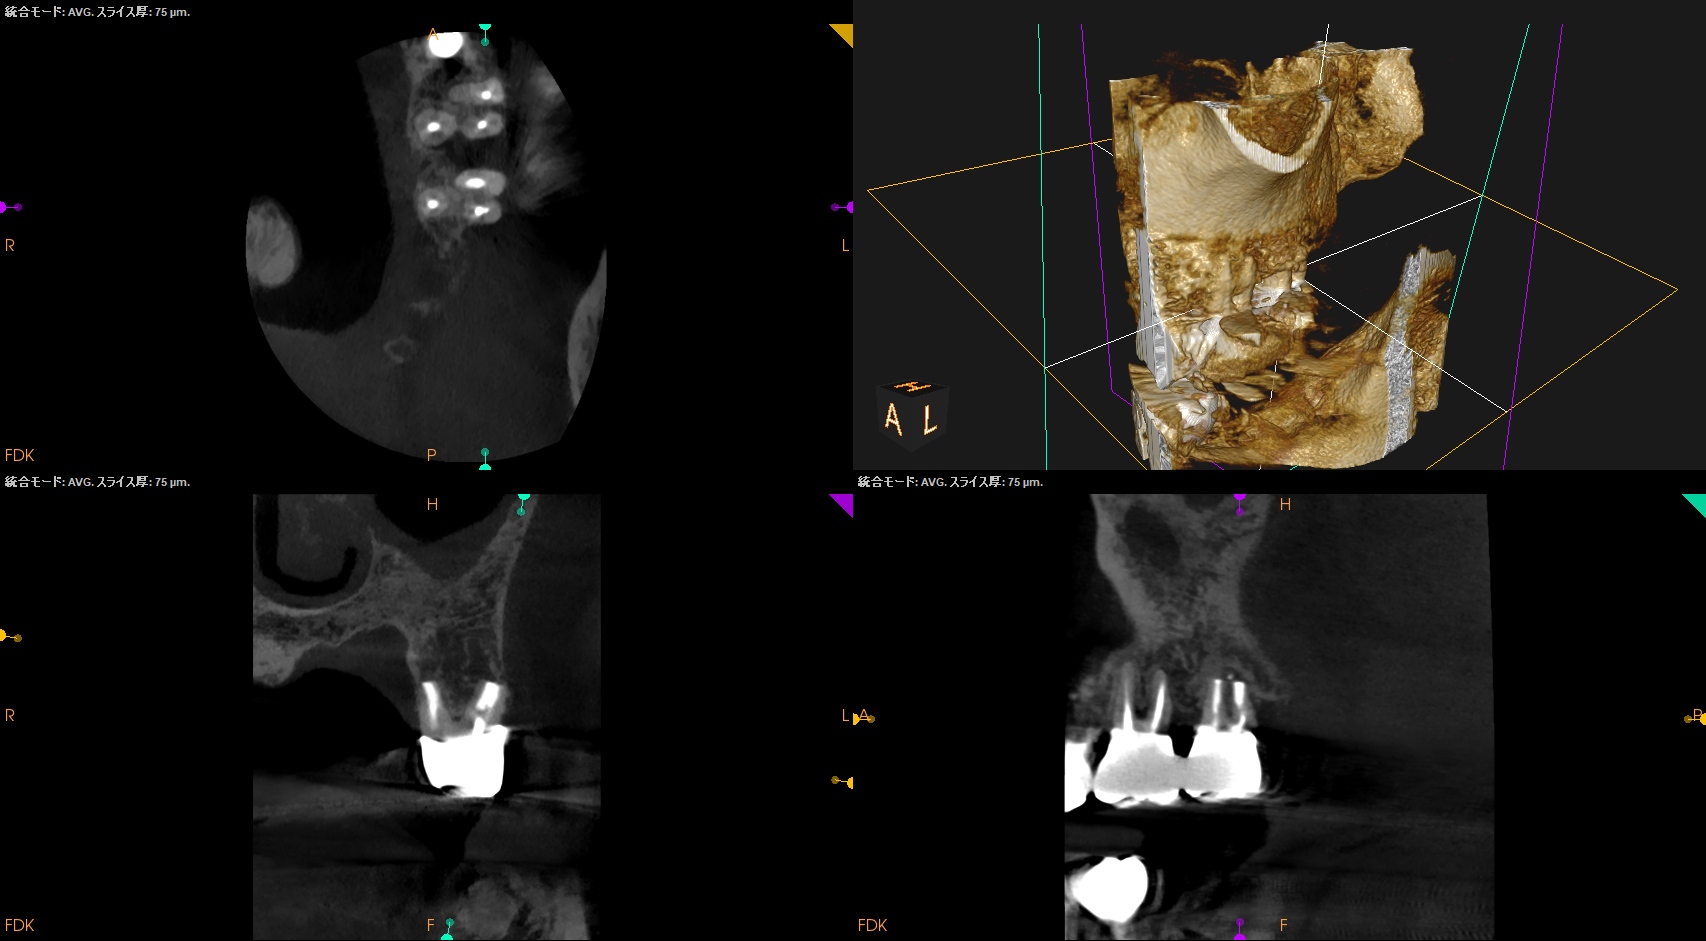

CBCTも撮影した。

MB

DB

P

術前と比較した。

ということで、臨床症状と術前/術直後の骨欠損(根尖病変)も消失し、歯槽骨が回復したため, この日で終診とさせていただいた。